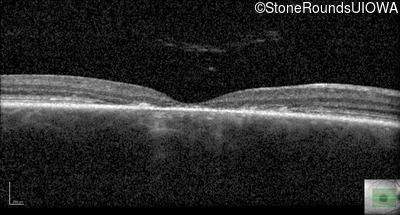

Optical Coherence Tomography - Right - 20/125 -1

Exemplar / OCT Stack